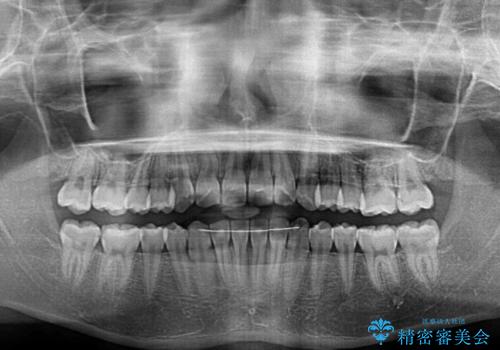

治療途中で大学受験があり、来院できない時期がありましたが、2年以内で満足のいく歯並びを達成することができました。